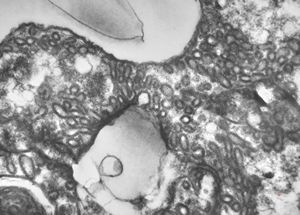

M,3m. | type II. pneumocyte

M,3m. | surfactant